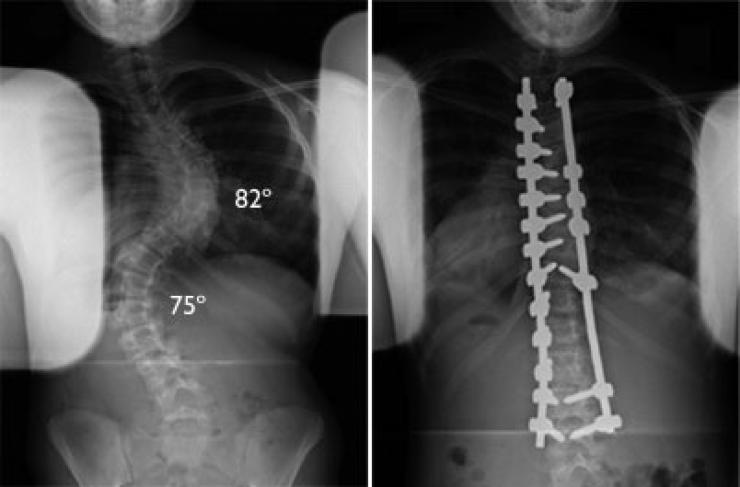

أعلن فريق طبي بمستشفى الكفيل التخصصي نجاحه بعملية تعديل إعوجاج العمود الفقري (سكوليوسز) لطفل بعمر سبعة أعوام، فيما أشاد ذوو الطفل بتكفل المستشفى بإجراء العملية بشكل مجاني. وقال رئيس الفريق الطبيب السوري، د. وائل قاسم اختصاصي جراحة العمود الفقري، ان فريقنا نجح بإجراء عملية لطفل بعمر سبعة أعوام يعاني من اعوجاج العمود الفقري (سكوليوسز). مبيناً "ان العملية إستغرقت قرابة الـ(9) ساعات واجريت بتقنيات طبية حديثة وفرها المستشفى، وإستعاد الطفل إستقامة عموده الفقري بشكل جيد. من جانبه قال والد الطفل ويدعى (م ـ ج)، ان المستشفى تكفل بإجراء العملية لولدي بشكلٍ مجاني بعد أن وجهت مناشدة لإدارته وتمت الإستجابة لي سريعاً. معرباً عن شكره للمستشفى لما يقدمه من خدمات مجانية للمرضى المحتاجين من مختلف محافظات البلاد، ومساهمته بمعالجة المرضى الذين لا يملكون ثمن العلاج وغير قادرين على السفر للعلاج في الدول الإخرى.